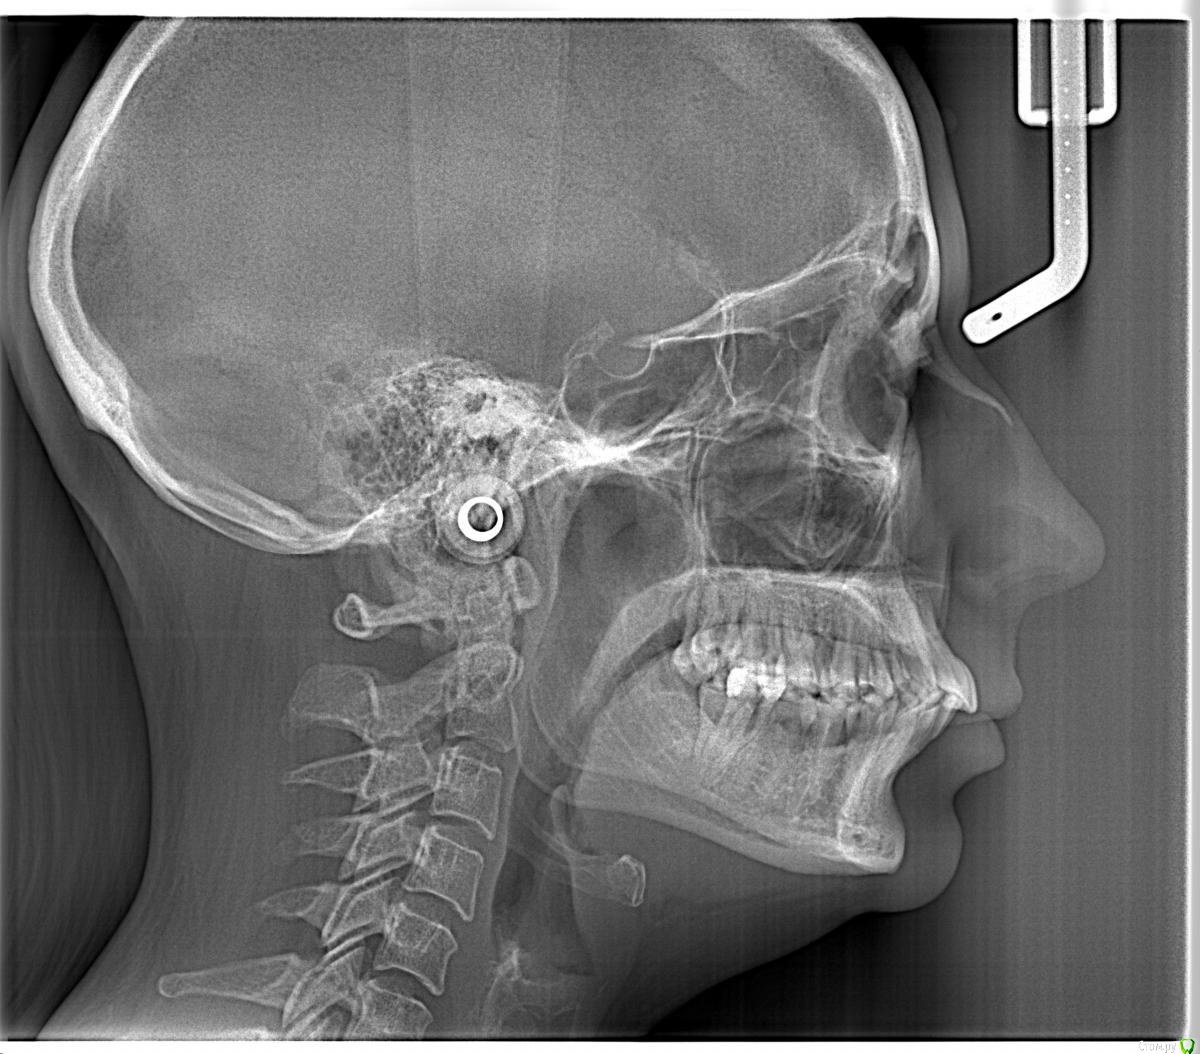

Yana guapa Опубликовано 13 мая, 2016 Поделиться Опубликовано 13 мая, 2016 Да нет, тут как раз проблема в зубах, так как из-за вторичной адентии 13 зуба фронт верха уехал вправо, да и правый боковой сегмент немного мезиализировался. Как тут поможет постановка челюсти в первый класс? Даже если бы вышеупомянутой проблемы по зубам не было бы, то для постановки челюсти эластиков скорее всего не хватило бы, а корректоры второго класса с таким пародонтом я ставить не рискнул бы.Вот в связи с этим и возник вопрос по первому классу, так как дистализировать не получится и удалять нельзя, потому что с таким пародонтом промежутки не закроются... Здесь чистый второй класс. Расчет ТРГ и индекс APDI Вам ясно это дают понять. конечно об эластиках речь не идет (я из вообще не применяю, только корректоры). Но не всегда первый класс - панацея. Зависит от того, какую вообще цель преследуете. Иногда можно оставить в привычном втором классе и со спокойной совестью отпустить)))))) Ссылка на комментарий

Opdihatop Опубликовано 13 мая, 2016 Автор Поделиться Опубликовано 13 мая, 2016 (изменено) Попова послушать лично не смогу. Я живу в Украине и он к нам, по понятным причинам, не приезжает (был когда-то на конгрессе, но там лекция по минивинтам была). 1) По ТРГ про второй класс я с Вами абсолютно согласен. Здесь главное, что волнует пациентку, это создание места под 13 зуб. Да, она согласна корректировать все остальные проблемы, но не пойдет на лечение, если "ее" цель не будет достигнута. И да, я понимаю, что идеала тут достичь у меня не получится.2) Так уж сложилось, что кросс-эластиками я не так уж много работал, как то пациенты не подворачивались. По-этому позвольте в связи с этим вопрос: а не навредит ли нам тут вестибулярный наклон верхних моляров, который несомненно возникнет за счет тяги (они наклонены орально незначительно)? Да, я понимаю, что и нижние наклонятся орально, но все же.3) Почему Вы против, пусть даже не сарпе, так хоть послабления небного шва в этом случае? С трудом верится, что в этом возрасте, пусть даже на самолигах, получится получить стабильное расширение.И последнее 4) Я встречал в литературе успешное применение, при подобном пародонте, дистализации на в/ч при непрямом анкораже на м/и. Подобное лечение (с нормальной костью) неоднократно производил и успешно. Как Вы считаете, рискнуть или успех маловероятен? Простите за сумбур, просто много мыслей в голове. Изменено 13 мая, 2016 пользователем Opdihatop Ссылка на комментарий